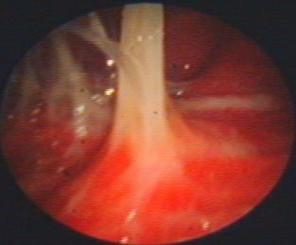

近年来,贵州航天医院各科室紧跟医学前沿,不断强技术、补短板,大力开展新技术、新项目,完成了许多高精尖、高难度、本地区“首例”的技术,填补了医院医疗技术空白,满足了群众日益增长的医疗需求。 贵州航天医院呼吸与危重症医学科是贵州省内呼吸疾病治疗规模最大,诊疗项目最全的呼吸疾病品牌科室,呼吸介入技术达到了全国先进水平,在贵州省内处于领先的地位。 本期,我们将为大家带来呼吸与危重症医学科特色技术——内科胸腔镜技术诊断和治疗胸腔疾病。 案例分享 患者苟某某,因劳累、气促,不明原因胸腔积液在某县一医院采取反复抽水等治疗手段效果不佳,当地医院考虑到患者年龄大(77岁),基础疾病较多,病情复杂,结合当地诊疗水平能力情况,建议转到上一级医院诊治,通过我院与该院建立的呼吸专科联盟绿色通道转入了我院。 患者入院后,呼吸与危重症医学科第一时间复查胸部CT,提示:右肺中叶、左肺感染,纤维化灶,左侧中量胸腔积液,右后侧胸膜轻度增厚,心包少量积液;并完善心电图、血常规、凝血功能、生化指标等术前检查。经科室专家团队集体讨论,得出患者左侧胸腔积液可能原因:结核?恶性?其他?冠心病、心功能不全、高血压病3级(高危组)、陈旧性肺结核复发?肺部感染;为进一步明确诊断,在充分评估、做好术前准备及应急预案、与患者及家属沟通的情况下,决定为患者进行内科胸腔镜检查术。 科室在患者入院第3天便实施了内科胸腔镜检查术,经检查取活检,病理不排除胸膜间皮瘤,送遵义医科大学附属医院病理会诊后诊断:胸膜间皮瘤。明确诊断后,科室专家团队为患者制定了个体化的治疗方案,患者病情很快得到有效控制,最终满意出院。半年后,医院通过电话回访,患者病情稳定,生活质量明显改善。 什么是内科胸腔镜 内科胸腔镜(medical thoracoscopy,MT)是一项微创诊断和治疗胸腔疾病的重要技术。主要应用于无创方法不能确诊的胸腔积液和胸膜疾病,通过局部麻醉后在胸壁做一个小切口,插入胸腔镜,直接观察胸膜、肺表面、纵隔等部位的病变情况,可进行活检、粘连松解及胸膜固定等操作。具有创伤小、恢复快、诊断准确性高等优点。 内科胸腔镜原理 内科胸腔镜是一项利用现代光学技术和成像技术的侵入性操作技术,应用电子支气管镜、硬质或软硬结合(半硬)的胸腔镜的一种电子内窥镜,末端装有连接着显示屏的微型摄像头。通过胸壁1-2cm左右的小切口,将内科胸腔镜及专用器械(戳卡套管)通过小切口进入胸腔,微型摄像头将胸腔内的情况投射到显示屏幕上,医生可以通过镜头全面、直观地观察患者胸腔内情况,了解胸膜病变确切位置和形态改变,还可对胸膜上的病变进行活检及治疗的操作技术,安全、微创、几乎无痛地“揭秘”不明原因的胸腔积液。 内科胸腔镜技术优势 (一)安全性高:仅需局部浸润麻醉,并发症发生率相对较低,对患者的身体条件要求较低。 (二)操作简便:操作时间短,痛苦少,患者耐受好。 (三)微创性:切口小,对患者身体损伤小,术后疼痛轻,恢复快。 (四)高分辨率成像:清晰显示胸腔内细微病变,提高诊断准确性。 (五)可直视操作:直接观察病变,进行精准活检和治疗。 (六)适用范围广:可用于不明原因胸腔积液、胸膜疾病、肺部疾病等的诊断和治疗。 (七)费用低:与外科胸腔镜比较费用低廉。 内科胸腔镜技术是贵州航天医院呼吸专科和呼吸介入诊疗优势的一部分,在2016年率先开展了内科胸腔镜技术,年手术量约100余例,已建立了快速、精准、规范、有效的一体化诊疗服务体系。目前呼吸与危重症医学科内科胸腔镜技术广泛应用于不明原因胸腔积液、气胸、脓胸的诊断和肺癌、弥漫性恶性胸膜间皮瘤等的分期,恶性或复发性胸腔积液、早期脓胸、自发性顽固性气胸的治疗。 镜下常见表现:单发或多发结节、灰白色弥漫性粟粒样结节、胸膜充血、水肿、胸膜增厚及纤维分隔或粘连带形成。 诊断方面: 胸腔积液的病因诊断。内科胸腔镜对恶性胸腔积液的诊断率可高达90%以上,胸腔镜对结核性病变诊断率极高,几乎达到96%以上。 腺 癌 恶性淋巴瘤 软骨肉瘤胸膜转移 滑膜肉瘤胸膜转移 结核性胸膜炎 治疗方面: 脓胸 肺大泡 贵州航天医院 呼吸与危重症医学科学科带头人 廖江荣 国务院政府特殊津贴专家 二级教授 主任医师 贵州航天医院副院长 国家级学术任职: 第二届中国医药教育协会介入微创专业委员会呼吸分会副主任委员 中国抗癌协会肿瘤微创治疗专业委员会常务委员 中国防痨协会结核病转化医学专业分会常务委员 第一届中国人体健康科技促进会呼吸介入专委会常务委员 中国医疗保健国际交流促进会结核病学分会第三届委员会常务委员 中国抗癌协会肿瘤微创治疗专业委员会粒子治疗学组第四届委员会委员 中华医学会结核临床专业委员会内镜介入委员 中华医学会放射学分会第十五届委员会介入学组呼吸系统介入专业委员会委员 北京健康促进会中青年专家委员会胸部疾病精准活检分委会副主任委员 中国医师协会介入医师分会第二届委员会肿瘤消融专业委员会委员 中国结核病防治综合质量控制专家指导委员会委员 亚洲冷冻治疗学会常务委员 世界内镜医师协会呼吸内镜协会常务理事 内镜临床诊疗质量评价专家委员会委员 “西部呼吸介入联盟”副理事长 专业擅长: 贵州航天医院 呼吸与危重症医学科简介 贵州航天医院呼吸与危重症医学科以呼吸危重症和介入呼吸病学为强力推手,以肺部感染性疾病及肺癌、肺小结节的早期精准诊疗、慢性呼吸疾病康复治疗为特色,以人才团队建设为核心的科室发展模式,现已成为省内呼吸疾病治疗规模最大,诊疗项目最全的呼吸疾病品牌科室。是贵州省医学重点学科、临床医学重点专科建设单位,遵义市首批呼吸重点学科、重点专科建设单位。是国家卫健委能力建设和继续教育肿瘤微创介入建设中心、贵州省县级医院微创介入培训中心、遵义市呼吸疾病临床医学中心。是国家呼吸医疗质量控制与管理哨点医院、遵义市呼吸内科专业医疗质量控制中心。是中国医药教育协会介入微创呼吸分会呼吸介入技术培训中心单位;国家卫健委海医会呼吸分会ROSE专委会“诊断性介入肺脏病学快速现场评价”培训基地;中国肺癌防治联盟“贵州航天医院肺结节诊治”分中心,中国人体健康科技促进会呼吸介入技术培训基地,贵州省中西医结合会呼吸学分会呼吸介入专委会主委单位。 基本情况 平均每年开展气管镜诊疗约4000例,经皮肺穿刺介入诊疗近千例,开展的项目包括经支气管镜(软、硬)下冷冻、氩气刀、高频电刀、球囊扩张、支架置入、超声内镜诊疗等气道介入诊疗技术,经皮肺穿刺活检及肿瘤消融术(微波、冷冻)、ROSE技术、内科胸腔镜诊疗及经血管介入诊疗技术,且多项呼吸介入诊疗技术在省内处于领先水平。 诊疗范围 航天医院呼吸专科擅长:致力于呼吸系统感染性、疑难性疾病的介入快速精准诊疗;肺癌与肺小结节早期精准诊疗水平项目提升。擅长于呼吸系统(肺)疑难病的诊断及危重病的救治,尤其在肺癌、肺小结节的早期诊断;肺癌综合靶向治疗;肺结核综合诊疗;肺部疾病的介入诊疗在省内处于前沿水平。 咨询热线 (一)呼吸与危重症医学科一病区 医生办公室:27677317 护士站:28614217 (二)呼吸与危重症医学科二病区 医生办公室:28691274 护士站:28690442 (三)呼吸与危重症医学科三病区 医生办公室:28692417 护士站:28690461 (四)呼吸与危重症医学科四病区 医生办公室:28616402、27677582 护士站:28614987、27677862